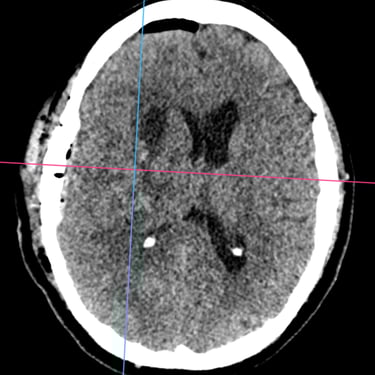

Hemorragia Intracerebral: Craneotomía y Evacuación del Hematoma

La hemorragia intracerebral es una emergencia neurológica grave que requiere diagnóstico rápido y tratamiento oportuno. Cuando el hematoma produce efecto de masa, deterioro del estado de conciencia o riesgo de herniación, la craneotomía y evacuación quirúrgica se convierten en la opción indicada. Este procedimiento permite abrir la bóveda craneal, retirar el coágulo y disminuir la presión intracraneal, preservando la función neurológica. Su objetivo es detener el daño secundario, mejorar la perfusión cerebral y estabilizar al paciente. La intervención temprana, combinada con cuidados críticos especializados, aumenta las posibilidades de supervivencia y recuperación funcional en este tipo de emergencia.